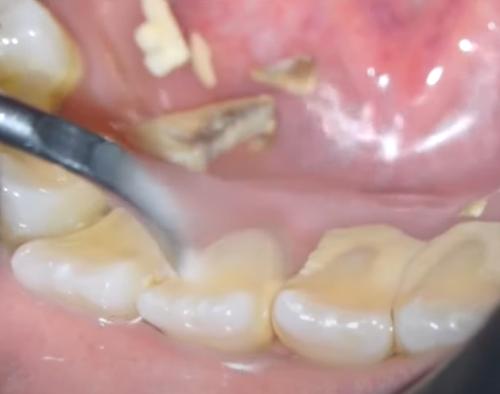

적절한 치아 위생을 실천하지 않으면 박테리아가 플라그 라고 하는 끈적끈적한 막으로 치아에 번식합니다. 플라그는 정기적으로 제거하지 않으면 결석이라고도 하는 치석으로 굳어집니다.

이것은 잇몸 라인 아래와 위의 단단하고 다공성인 물질입니다. 도달하기 어려운 부위와 치조골은 치석 축적이 발생할 위험이 더 큽니다. 치석이 쌓이면 굳어 일반 칫솔로는 더 이상 제거할 수 없습니다.

치아에 치석이 보인다면 박테리아가 끊임없이 법랑질을 먹고 있다는 뜻입니다. 그리고 당신은 그것을 닦거나 긁어낼 수 없습니다. 이는 치석이 제거될 때까지 손상이 계속 발생한다는 것을 의미합니다.